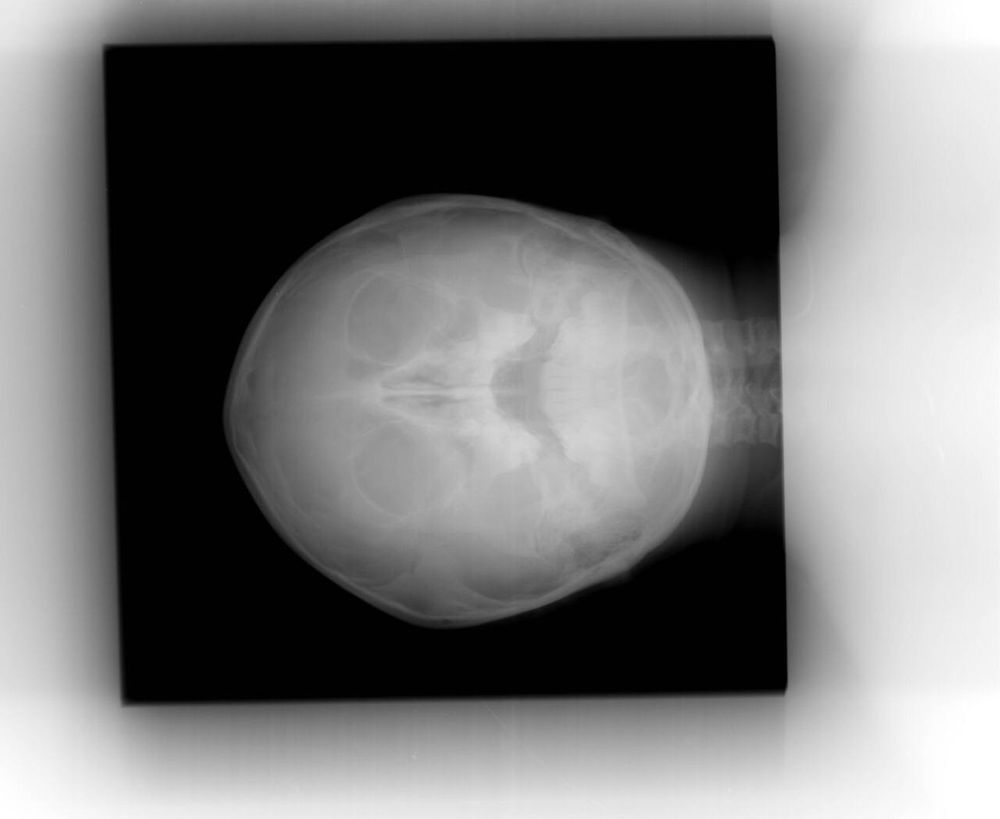

Сделали рентген, снимок не отдали только заключение - затемнение в правой пазухе, правосторонний гайморит. назад к лору - назначила лечение. Домой вернулись, аппетита нет, лег спать, а/б от лора на ночь принял.

Мне говорят мол вы что гайморит это серьезно очень там рядом мозг и все такое, а тут выходные на носу, едте в подольск они там на месте разберутся к лору вам или к стоматологу там все рядом. Выписали направление и сказали снимок получить вчерашний. Снимок распечатать не смогли мне, только вечером смогут, но скинули в на почту электронку. в Странном формате, что б его открыть на телефоне я переотправляла мужу он на компе открыть накрутил нормальный контраст и в др формате пересохранил и мне отправил уже. Сама я ничего особенного не увидела на том снимке но ок - я не врач. Едем в подольск. в подольске охеренная очередь с такими же направлениями в лор отделение... кому то ложиться кому то на консультацию. еще кто-то по скорой между нами без очереди попадает.

Попадаем к лору - показываю снимок на телефоне какой уж есть. Он не считает что это гайморит, но раз уж мы там и его сюда направили надо исключить. Пункция пазухи через нос и промывание - гноя нет, но промывается плохо или туго как то так он сказал - воспаление есть. Но нам не сюда а в челюстно-лицевое. Ждем заключение и идем туда. Еще одну очередь стоять/сидеть.